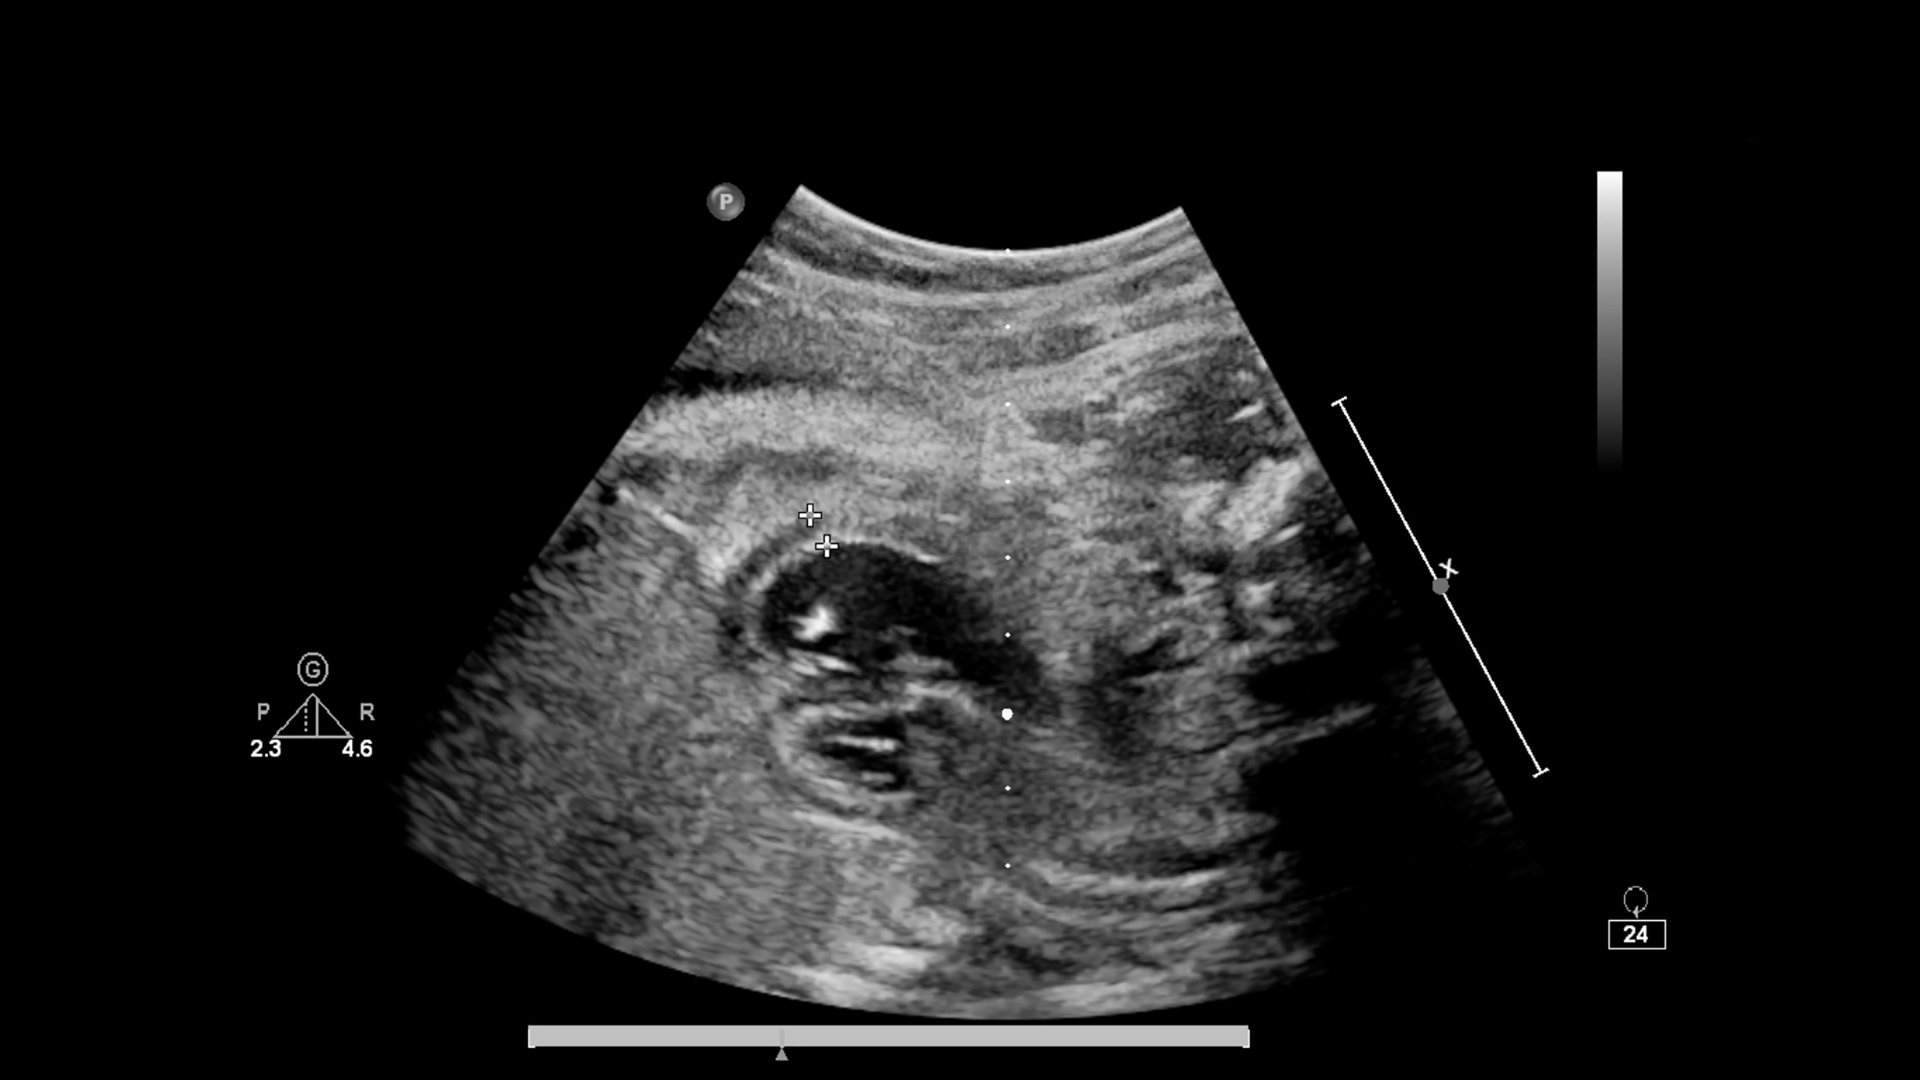

Sau khi bơm IUI, tinh trùng được đưa thẳng vào tử cung nên quãng đường di chuyển được rút ngắn đáng kể. Từ đây, tinh trùng sẽ bơi lên ống dẫn trứng để tìm trứng. Nếu trứng đã rụng hoặc sắp rụng đúng thời điểm, tinh trùng có thể gặp trứng chỉ sau vài giờ. Trong trường hợp trứng rụng muộn hơn, tinh trùng vẫn có thể chờ sẵn và gặp trứng trong khoảng 2 đến 3 ngày sau bơm.

Dù quá trình tinh trùng gặp trứng diễn ra khá nhanh, phôi sau khi được hình thành vẫn cần thêm vài ngày để di chuyển về tử cung và bám vào niêm mạc để làm tổ. Đây là giai đoạn rất quan trọng, quyết định việc thai có phát triển ổn định hay không.

- Ngày 4 đến ngày 5: Nếu trứng và tinh trùng gặp nhau thành công, quá trình thụ tinh diễn ra tại vòi trứng. Lúc này phôi bắt đầu di chuyển chậm về phía buồng tử cung.

- Ngày 6 đến ngày 12: Phôi thai bám vào niêm mạc tử cung để làm tổ. Một số người có thể thấy vài giọt máu hồng nhạt hoặc nâu nhạt xuất hiện trong thời gian ngắn.